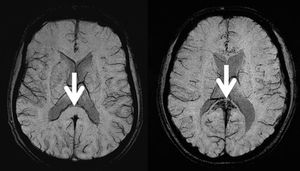

CHICAGO - High-altitude cerebral edema, the end stage of severe acute mountain sickness - once thought to be reversible - causes microbleeding on the brain.